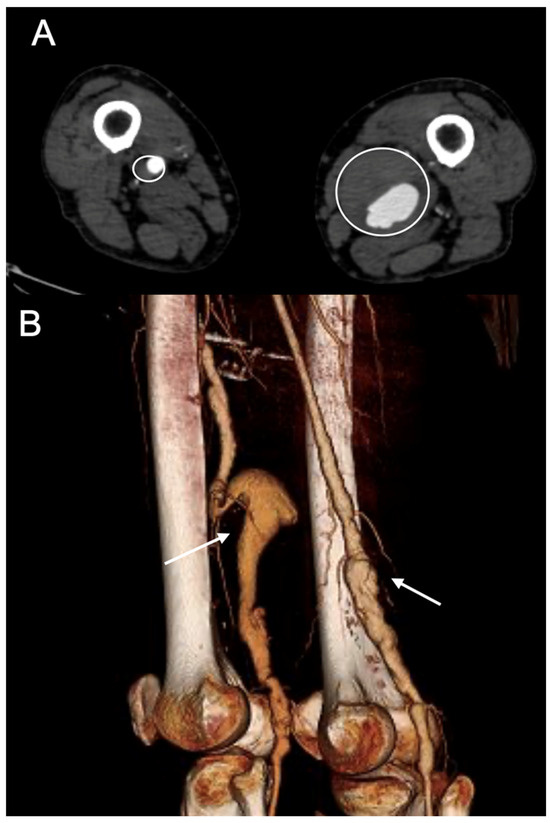

Figure 2. Preoperative computed tomography angiography of a patient presenting with a bilateral PAAA treated at our institution. (A) A case of bilateral popliteal artery aneurysm (PAA) treated at our institution. A transversal slice of the preoperative CTA (circles) and a 3D reconstruction (B) (arrows).

The inclusion criteria were as follows: (1) PAA > 20 mm in maximal diameter, (2) aged >18 years, (3) diagnosis confirmed by a contrast-enhanced computed tomography angiography (CTA), and (4) elective surgical treatment (Figure 2).